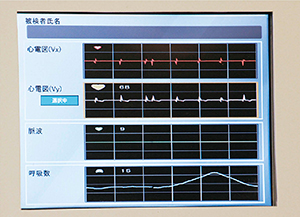

検討会では,収集したデータから課題が洗い出され,ソフトウエアや撮像法など,多角的に改良がなされていった。検討において最も難しかったのは,心拍数と呼吸が撮像に及ぼす影響を解析することだったと熊谷技師長は話す。

「検討していく中で撮像に最も影響するのが心拍数と呼吸であることがわかりましたが,これらと画像の関係を検証することが大変でした。モニタに録画機を接続して,検査中に呼吸状態や心拍数がどのように変化するかを記録し,落合先生が1つ1つ画像と照らし合わせて細かく検証していきました。心拍数については,薬によるコントロールをせずにどこまで撮像可能かを検討したところ,心臓CTよりも高い75〜80bpmでも撮像できることがわかりました」

一方,呼吸については,ECHELON OVALに搭載された呼吸同期機能“横隔膜ナビ”のさらなる改良が求められた。課題と要望が日立メディコの開発部門にフィードバックされて改善が図られたことで,同期のためのデータの検出精度が大きく向上し,呼吸が安定しない被検者での成功率を効率的に向上させることにつながった。

ECHELON OVAL本体のWIT Monitor |